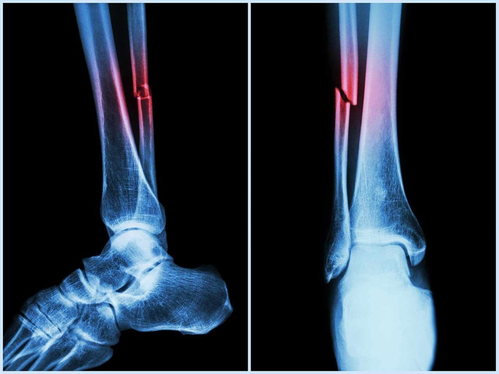

New Delhi: Researchers from the National Institute of Technology (NIT) Rourkela have uncovered how natural sugar-like molecules in the human body can alter the behaviour of a protein responsible for bone formation and repair.

In this context, Bone Morphogenetic Protein-2 (BMP-2) plays a crucial role in forming bones and cartilage, healing injuries, and guiding stem cells to become bone-forming cells, said the team from NIT.

The research insights can help in developing improved biomaterials and drug delivery systems for the treatment of bone fractures, spinal injuries, and degenerative bone diseases. It can also aid in optimising drug delivery during treatment and reducing side effects for patients.